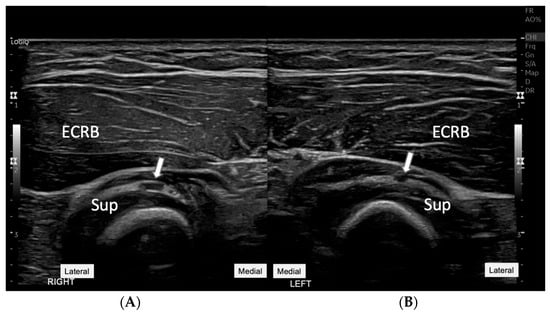

Figure 3. Comparative ultrasound images of the affected right forearm (A) with the unaffected left side (B). This figure presents side-by-side images of both the right and left forearms, specifically focusing on the region of the supinator muscles. The arrows on each image point to the PIN as it courses through the supinator muscle (Sup). On the right side (A), there is a noticeable swelling of the PIN at the site of the lesion. In contrast, the left side (B) shows a normal appearance of the PIN without swelling, serving as a control reference. This comparative view underlines the diagnostic value of ultrasound in assessing asymmetrical nerve conditions and supports clinical findings of neuropathy on the affected side. ECRB: Extensor carpi radialis brevis. An ultrasound-guided aspiration was performed, carefully avoiding the PIN (Figure 4). The precision of the procedure, with the aspiration needle positioned to avoid nerve structures while targeting the cyst, was critical [3]. The aspiration yielded a clear synovial fluid, which not only confirmed the nature of the cyst but also relieved pressure on the PIN. The differential diagnosis for the mass included conditions such as lipoma, rheumatoid nodule, and other inflammatory processes like bursitis or abscess formation, which typically present with a different echogenicity pattern, helping to rule them out in this case [4,5].